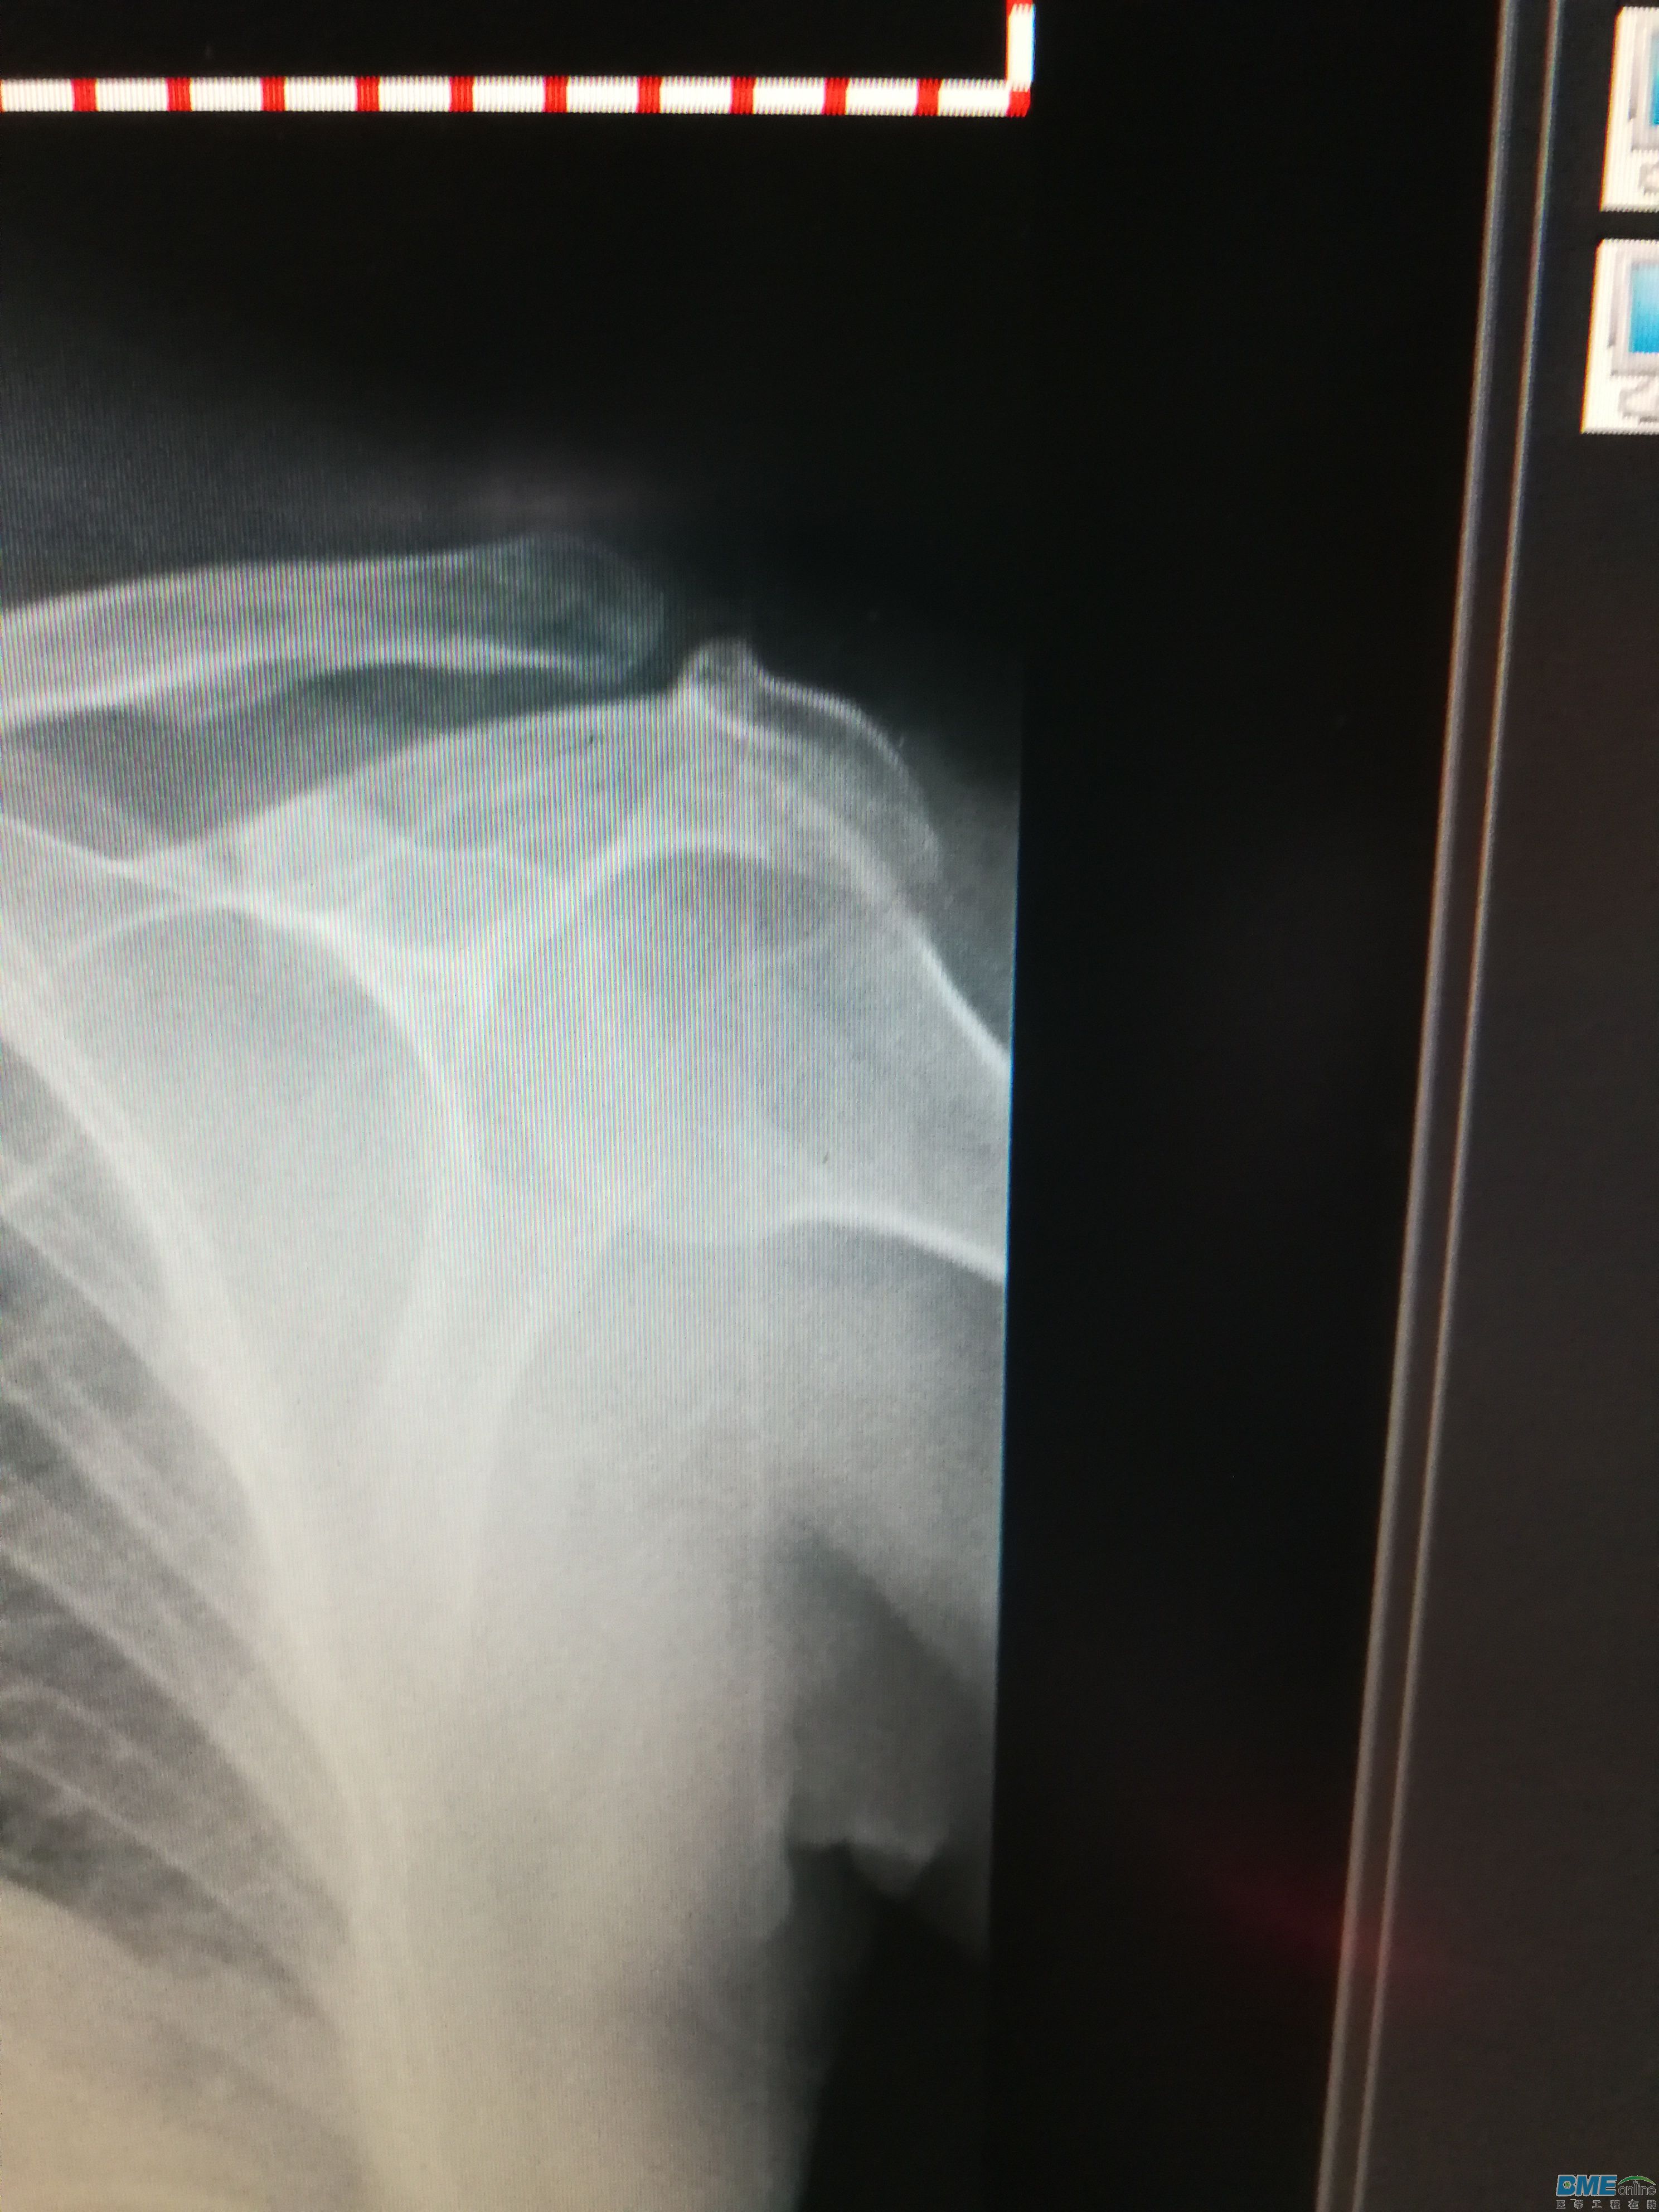

柯达IP影像板出现一条粗细相同的白色伪影该怎么处理?这个IP板还有补救办法吗?